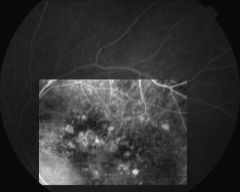

IM000014